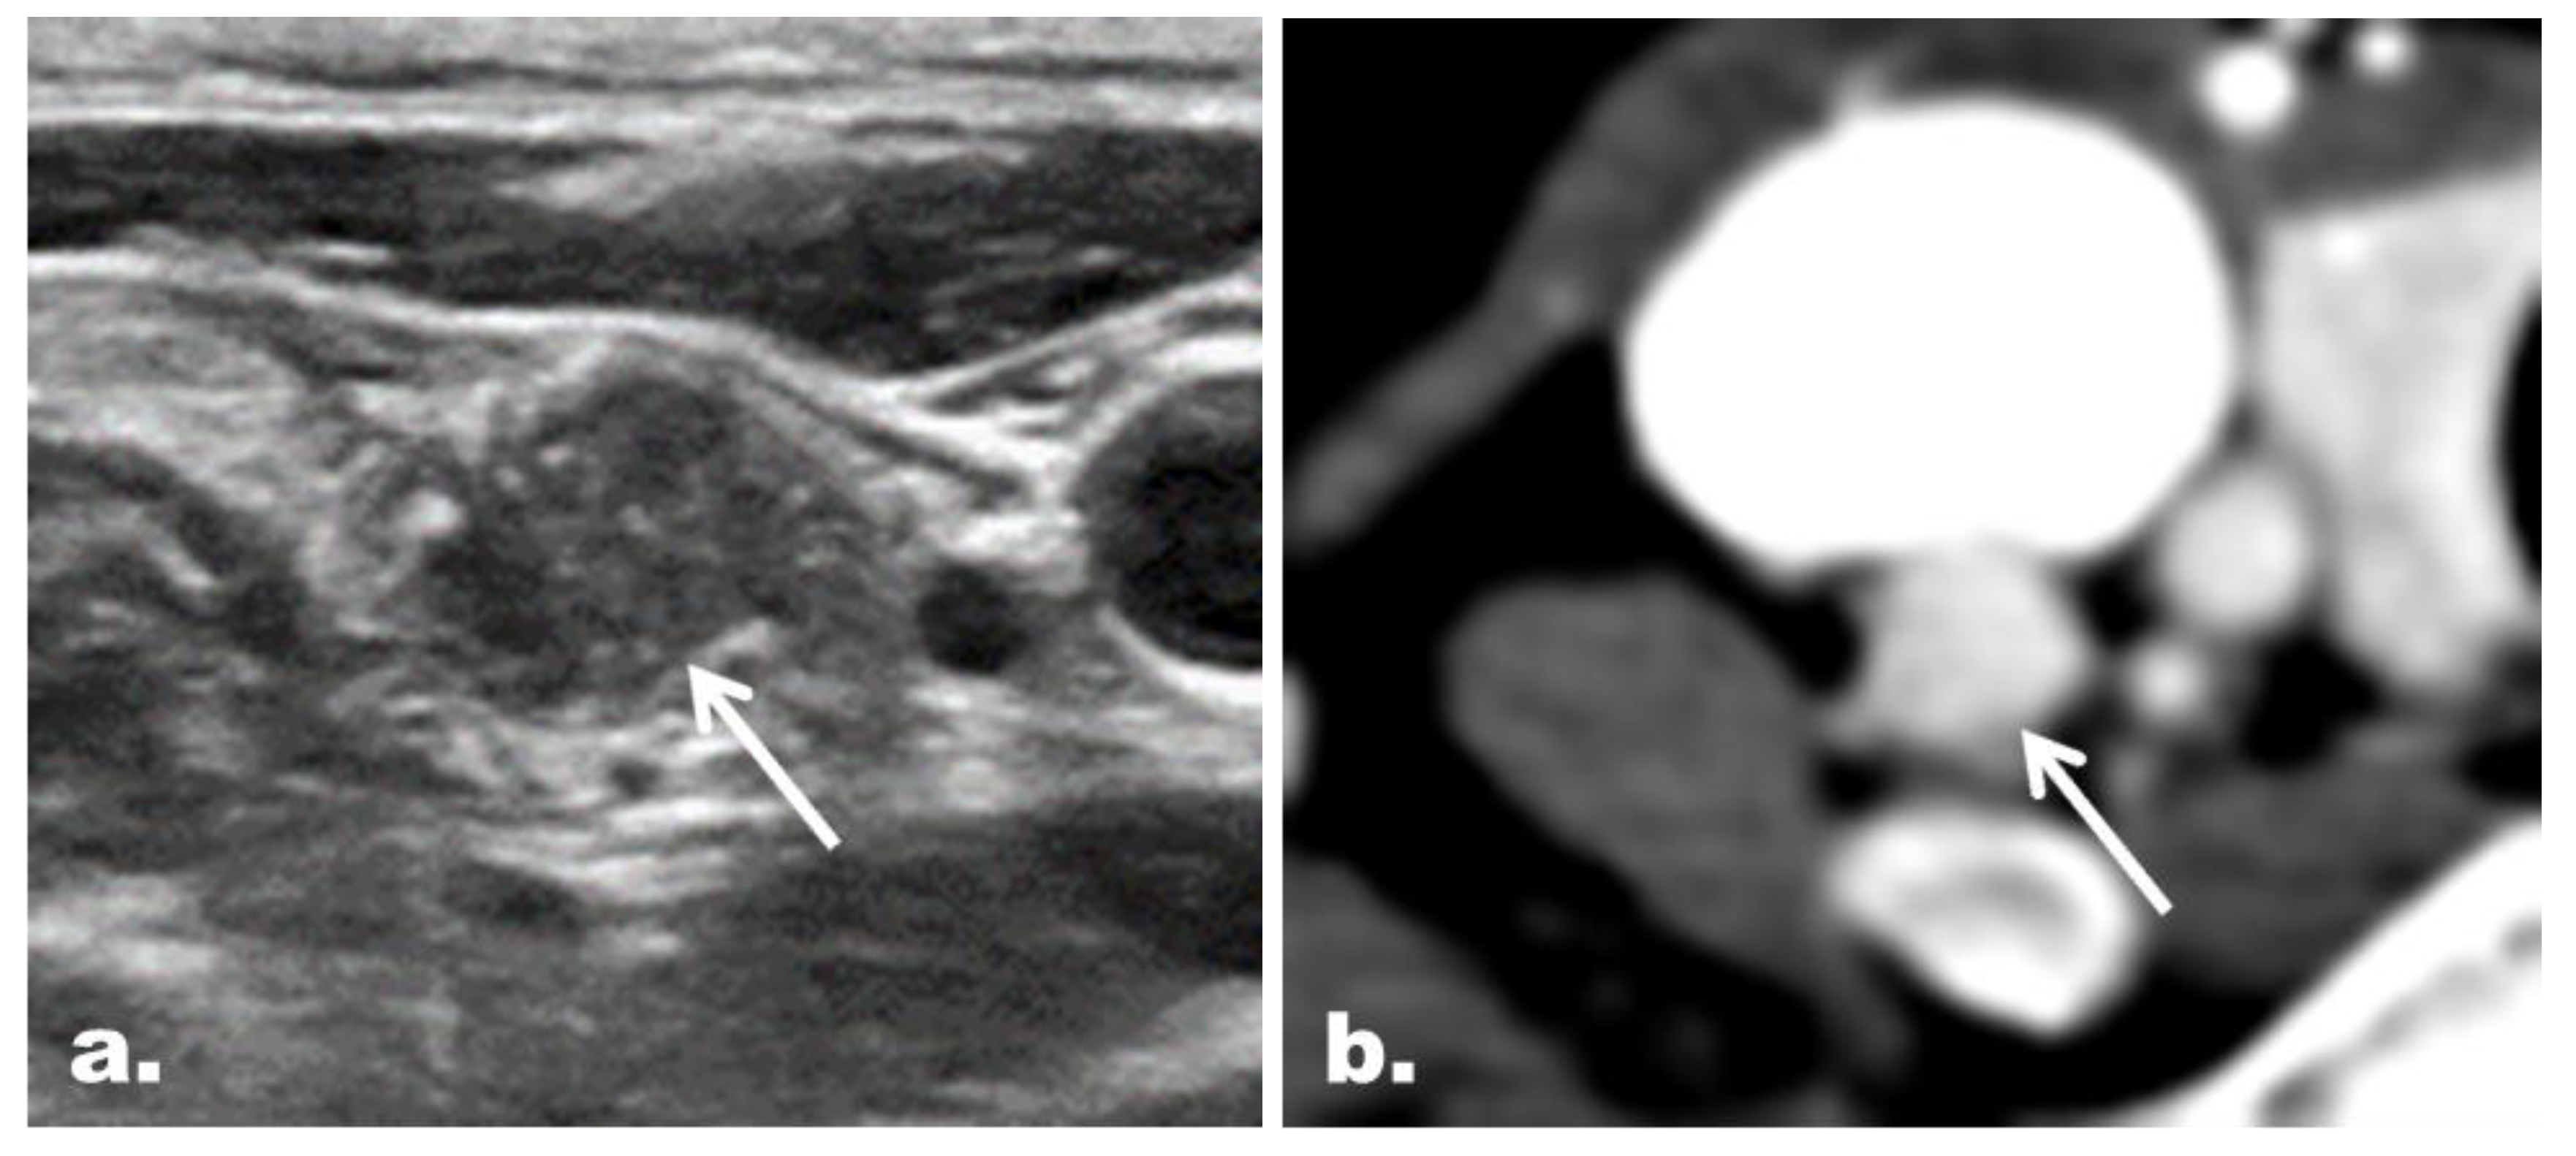

2.5. CT Imaging Features in the Reclassified Cases